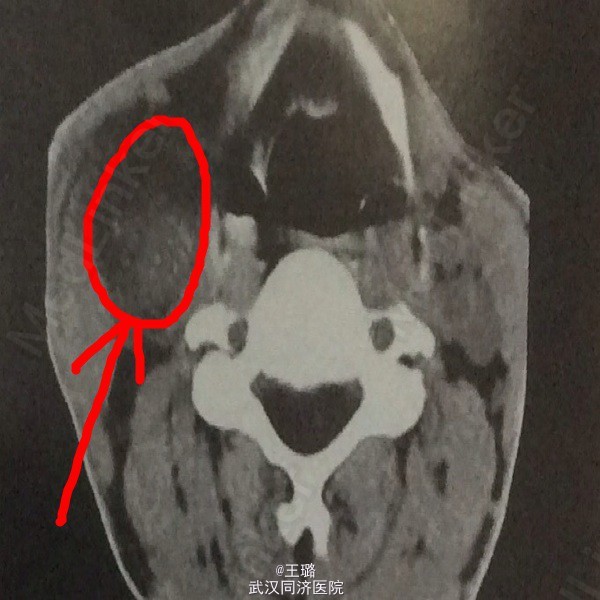

患者,男,37岁,发现右颈部肿物、眼睑下垂一月入院。体检可闻及颈部血管杂音,眼睑下垂,面部表情淡泊,高血压。实检:电解质正常,白蛋白降低,血肌酐正常。颈部CT示:右颈部颈动脉分叉处见卵圆形软组织占位,密度不均匀,周围组织和器官有受压。增强CT:肿块明显强化,与动脉强化程度相仿。遂给予手术治疗,病检示:颈动脉瘤。其为发生于颈动脉体化学感受器的肿瘤,多为良性,压迫血管可闻及杂音,压迫颈交感神经可出现Horner综合征。